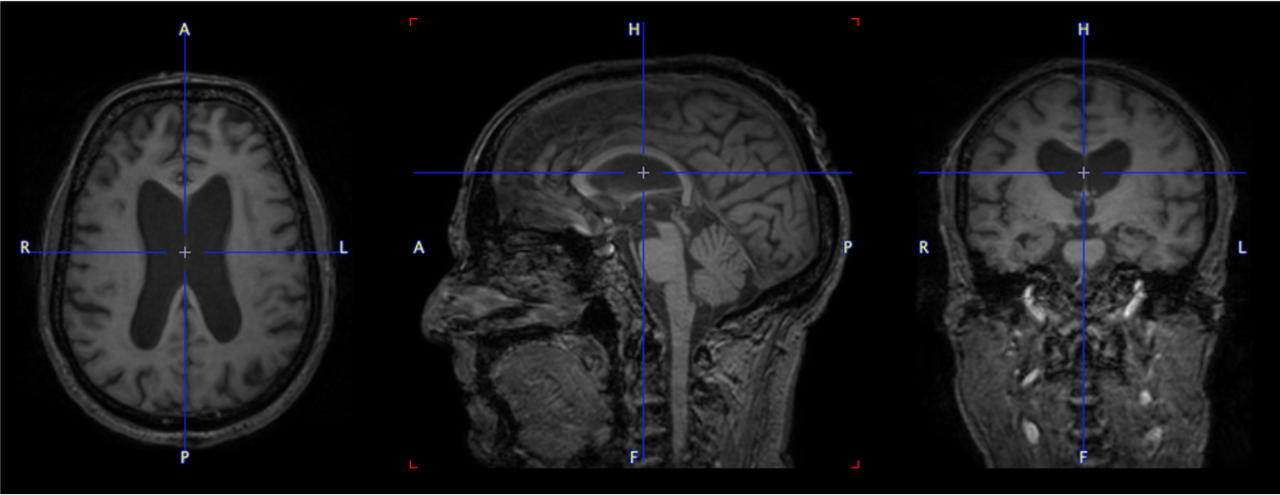

pmod’s tools provide comprehensive workflows for post-processing and quantification of imaging data for fundamental oncology research, development of radiotracers and theranostics, and in clinical research studies. Imaging scientists can trust pmod to reproducibly read their data, interpret the meta-data/units and help users calculate statistics such as SUV for their studies and publications.

• Multimodality segmentation tools – comprehensive semi-automated and manual tools for precision and reproducibility

• Flexible switching between 3D and 4D datasets – direct output of time activity curves